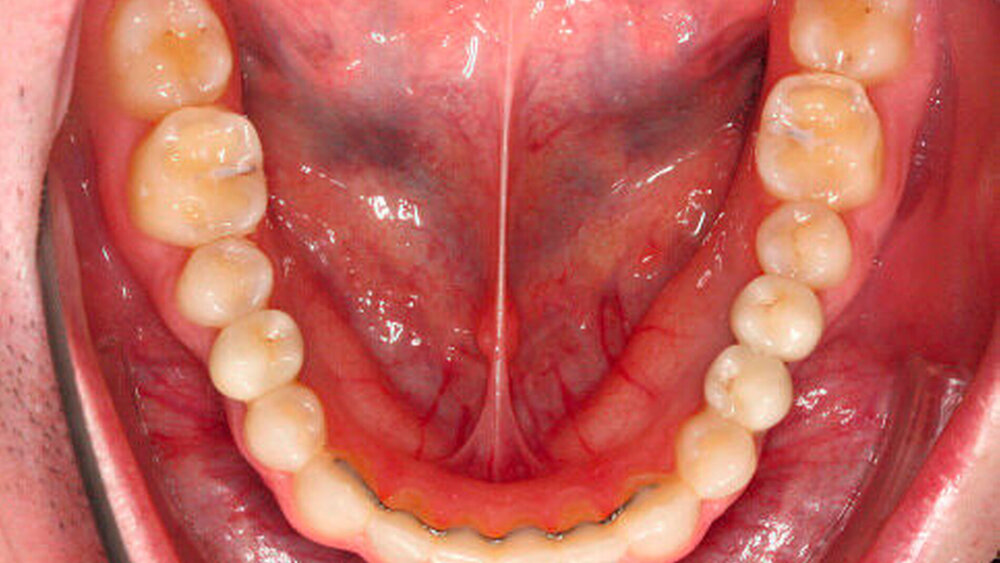

Der kieferorthopädische Befund ergab ein Missverhältnis zwischen Zahn- und Kiefergröße aufgrund der vorliegenden relativen Mikrodontie. Dabei zeigten sich lückige, leicht protrudierte Fronten und weitere Lücken in beiden Kiefern (Abbildung 3).

Der Platzüberschuss lag im Oberkiefer (OK) bei +18,7 mm und im Unterkiefer (UK) bei +17,2 mm, zudem bestand eine Unterkieferschwenkung nach links bei einem Distalbiss mit Gleiten zwischen Zentrik und habitueller Interkuspidation. Der Zahn 13 war verlagert.

Der Patient war zu diesem Zeitpunkt entbändert und trug, sowohl im Oberkiefer als auch im Unterkiefer, einen festsitzenden Retainer zur Langzeitstabilisierung (Abbildungen 15 bis 18).